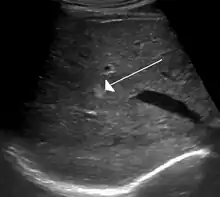

A cavernous liver hemangioma or hepatic hemangioma is a benign tumour of the liver composed of hepatic endothelial cells. It is the most common liver tumour, and is usually asymptomatic and diagnosed incidentally on radiological imaging. Liver hemangiomas are thought to be congenital in origin.[10] Several subtypes exist, including the giant hepatic hemangioma, which can cause significant complications.

Diagnosis is usually clinical. Paediatric dermatologists are experts in diagnosing and treating hemangiomas. Depending on the location of the hemangioma, tests such as MRIs or ultrasounds can be done to see how far the hemangioma goes under the skin and whether it affects any internal organs.[12]